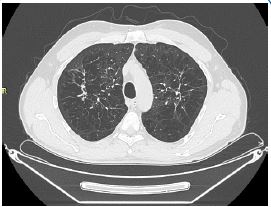

A 56-year-old Caucasian man, former smoker (23 pack years), with a diagnosis of Langerhans Cell Histiocytosis on lung biopsy since about 20 years and in treatment at the Histiocytosis Center of the Policlinico Umberto I, was referred to the Rare Lung Disease Clinic of the Policlinico Umberto I for a clinical picture characterized by dyspnea for mild exertion (MMRC 2). On chest auscultation, reduced physiological respiratory noises were present bilaterally over the entire lung area, but pathological noises were absent. The cardiological objective examination was normal. SpO2 in room air was 97%. Global spirometry (Figure 1) showed mild obstructive ventilatory deficit (FEV1/FVC 62.8, FEV1 3.07 L - 85%), with air trapping indices at nitrogen wash out test (RV: 154%; RV/TLC: 41.3). DLCO was 23.32 ml/min/mmHg, at the lower limits of normal (77% of predicted). An HRCT was performed (Figure 2) showing centrolobular and paraseptal emphysematous lesions with associated destruction of interlobular and interlobular septa, with greater distribution in the upper lobes and middle lobe. In the upper lobes multiple pseudo- nodular lesions were present in continuity with retracting fibrotic striae and traction bronchiolectasis. Because of the presence of a significant amount of emphysematous lesions, although in nontypical lung regions, we decided to assay serum alpha1-antitrypsin, which was found to be 78 mg/dL (PCR 0.13 mg/dL). These values revealed the presence of an intermediate A1AT deficiency.

Figure 2: The following HRCT showed the presence in the posterior and anterior segments of the right and left upper lobe of panlobular and paraseptal emphysematous bullae, associated with pseudo-nodular areas in continuity with retracting fibrotic striae and traction bronchiolectasis.